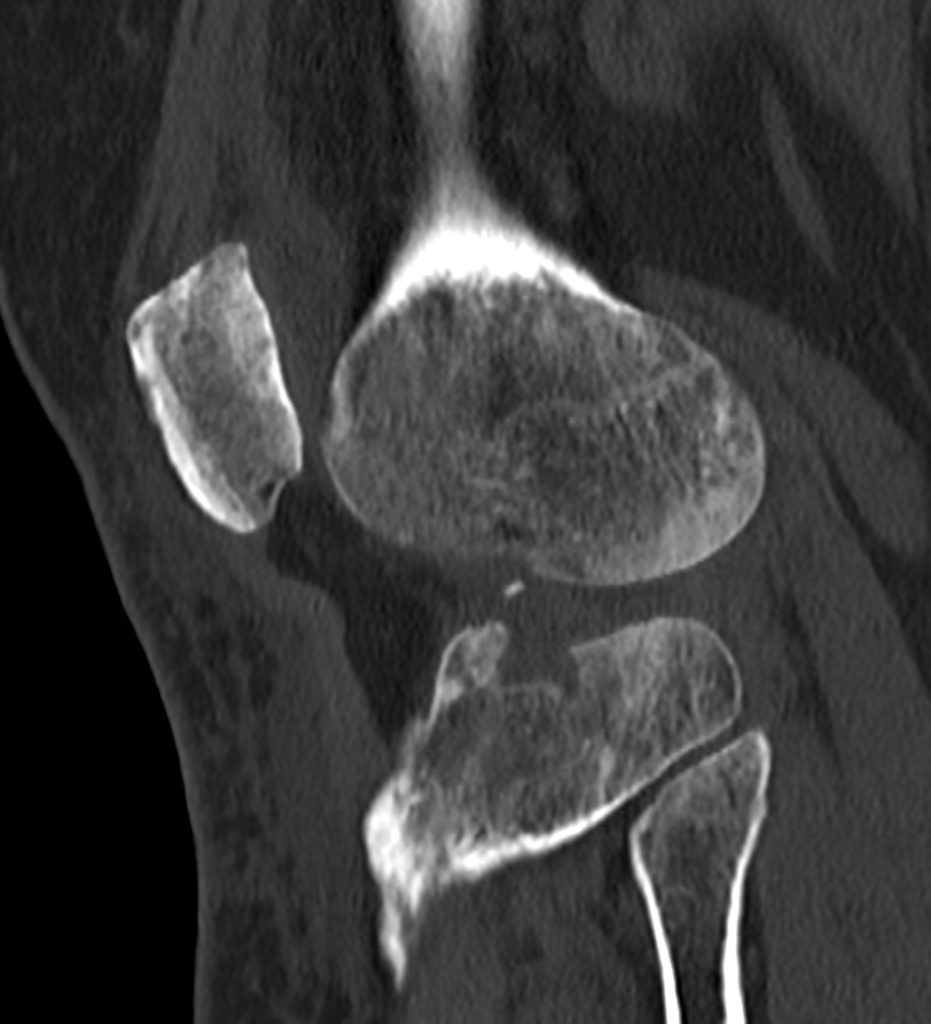

سي تي اسکن اسپيرال زانوي راست ( مولتي ديدکتور 16 با مقاطع ظريف و بازسازي هاي ساژيتال و کرونال و 3D):

– دفورميتي پلاتوي لترال تيبيا ناشي از depressed Fx و فرورفتگي در سطح مفصلي پلاتوي لترال

– نشانه هاي cortical Fx بدون جابجايي در کنديل لترال فمور

– loose body استخواني به ابعاد mm 2 x 3 در انترولترال مفصل زانو و

– افيوژن خفيف در مفصل زانو همراه با تورم نسج نرمي در اطراف آن

مشهود است .